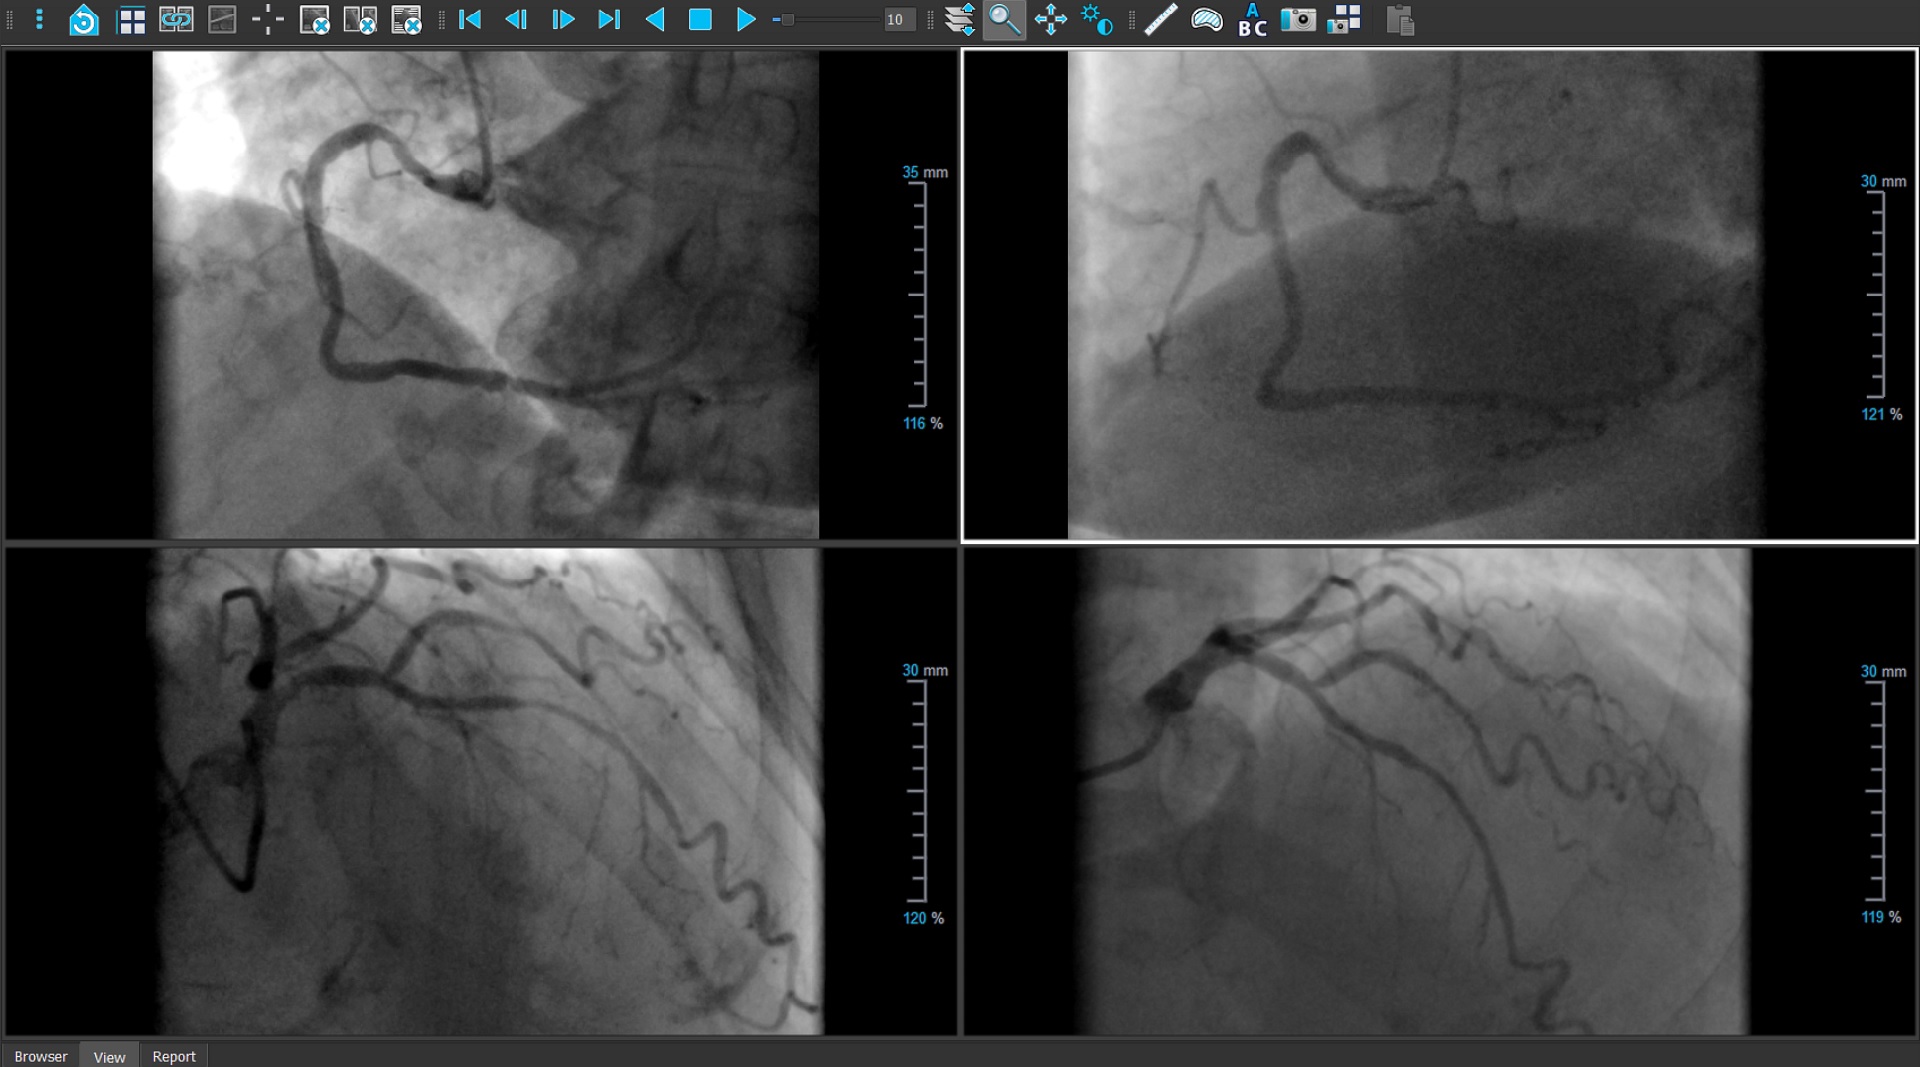

QAngio XA 3D is the analytical software solution for the reconstruction of a coronary artery from two X-ray angiographic projections at least 25 degrees apart - either from biplane or monoplane X-ray systems - and the subsequent QCA analysis of clinically relevant parameters of coronary obstructions. It is the backbone for subsequent PCI treatment: QAngio XA 3D provides all the anatomical parameters for stent sizing, the optimal viewing angles for visualizing the lesion area, and the physiologic assessment (QFR) of one or more lesions at the same time.